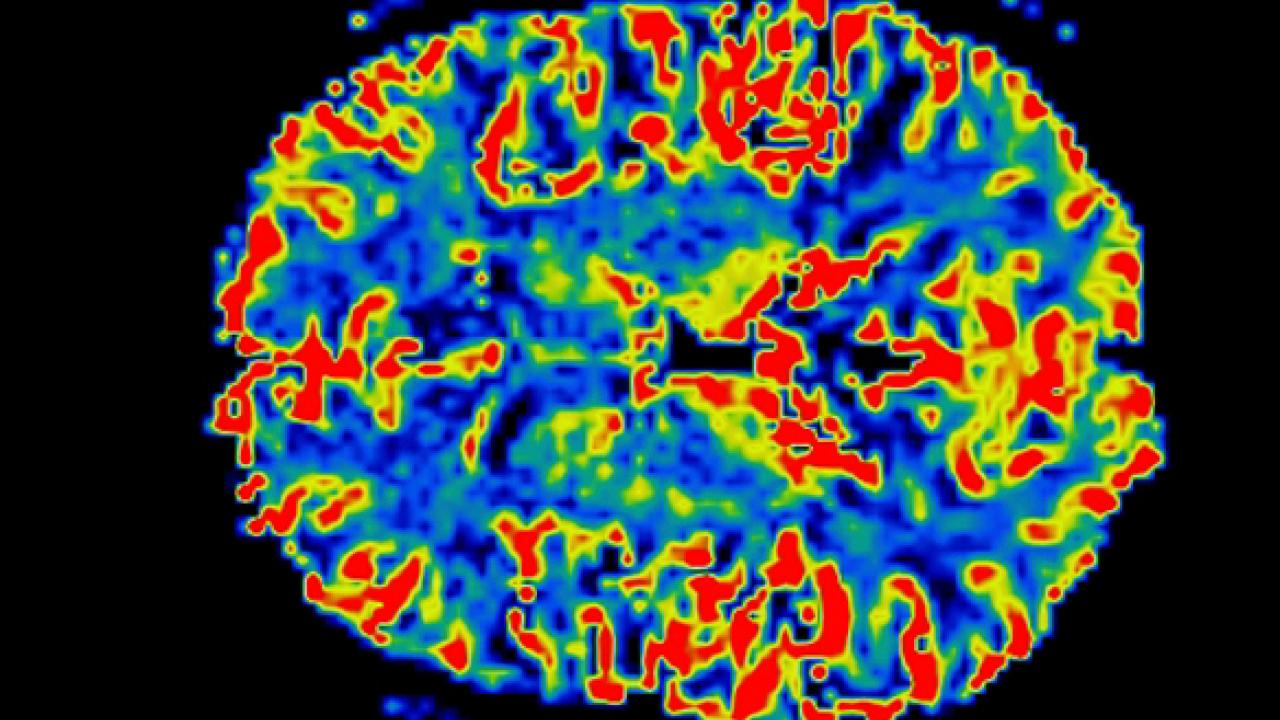

IJMS Free FullText Neuroinflammation in Parkinson’s Disease From Parkinson's Disease Autoimmune A recent gwas identified 17 shared loci between pd and 7 autoimmune diseases, including type 1 diabetes, crohn’s disease,. Recently, several notable data have highlighted various immune alterations underlying that pd is associated to autoimmune features and could. Parkinson’s disease (pd) is a neurodegenerative disorder, caused by, so far, unknown pathogenetic mechanisms. The first symptom may be a barely noticeable. Parkinson's Disease Autoimmune.